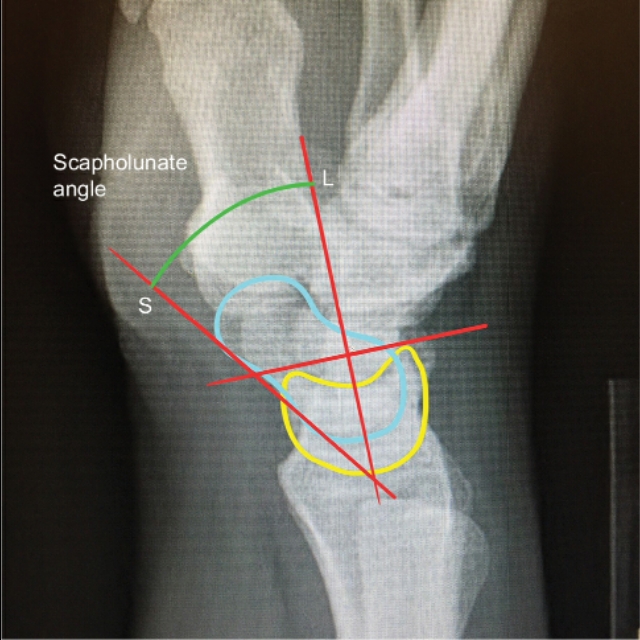

病人被置于仰卧位,在透视下,手被过伸牵引。这个位置扩大了舟骨和大多角骨的间隔,改善了对舟骨远极的可接近性(图1A和B)。在大多数情况下,纵向牵引足以复位骨折(在单独牵引不足的情况下,可使用克氏针作为操纵杆将骨折碎片操纵至其原始位置)。一旦通过透视检查确认复位,最重要的步骤是确定导丝的入口点和螺钉的位置。 这个入口点是舟状骨结节,它可以通过腕关节背身弯曲成90°,插入舟状多角骨关节的12-14号注射器针头定位。这根针头被撬入小多角骨,使舟骨的远端更为偏桡侧,有助于导丝的插入(图1C)。

理想的起点距离舟状骨结节顶点约2毫米(以实现骨路径内的最大导丝长度) 。一旦确定了方向和入口点,导针就被置入到关节中,这样碎片就不会在导丝通过过程中移动。引入导丝,并通过图像增强器连续评估其方向,以便将导丝送到近端(图1D和E)。如果导丝处于满意的位置,做一个大约0.5cm的纵向切口,用止血器探查,直到舟状骨结节。 螺钉的长度由测深确定,短4–5 mm以获得正确的测量值 。 在少数情况下,可以使用第二根克氏针以避免碎片旋转。 取下针头,用空心钻穿过导丝,距关节面约2 mm。压缩螺钉穿过导丝,并用图像增强器检查其末端位置。然后关闭切口(图1F)。

将患者置于仰卧位,手臂伸直放在手术台上。影像增强器垂直于手腕放置。为了导丝的通过,在将舟状骨的中心轴定位在前后视图上之后,手腕旋前并弯曲45度或更大,直到舟状两极进入直线(图3A)。

然后通过皮肤上的一个小切口,向舟状骨顶点(仅被背侧关节囊和皮下组织覆盖,通常在其路径上没有肌腱或神经)方向, 沿舟状骨月骨韧带桡侧1-2 mm将一根1 mm的导丝引入。 12或14号针可用于帮助通过导线(图3B-E)。如果没有达到合适的位置,可以使用较粗的导线(例如1.5 mm)。引入空心钻头(图3F),并使用比测量长度短4-5mm的螺钉,因为生物力学研究表明,螺钉越小,固定效果越好。用图像增强器评估最终螺钉位置和骨折压缩(图3G-I)。术后仅使用敷料和弹性绷带(图3J)。